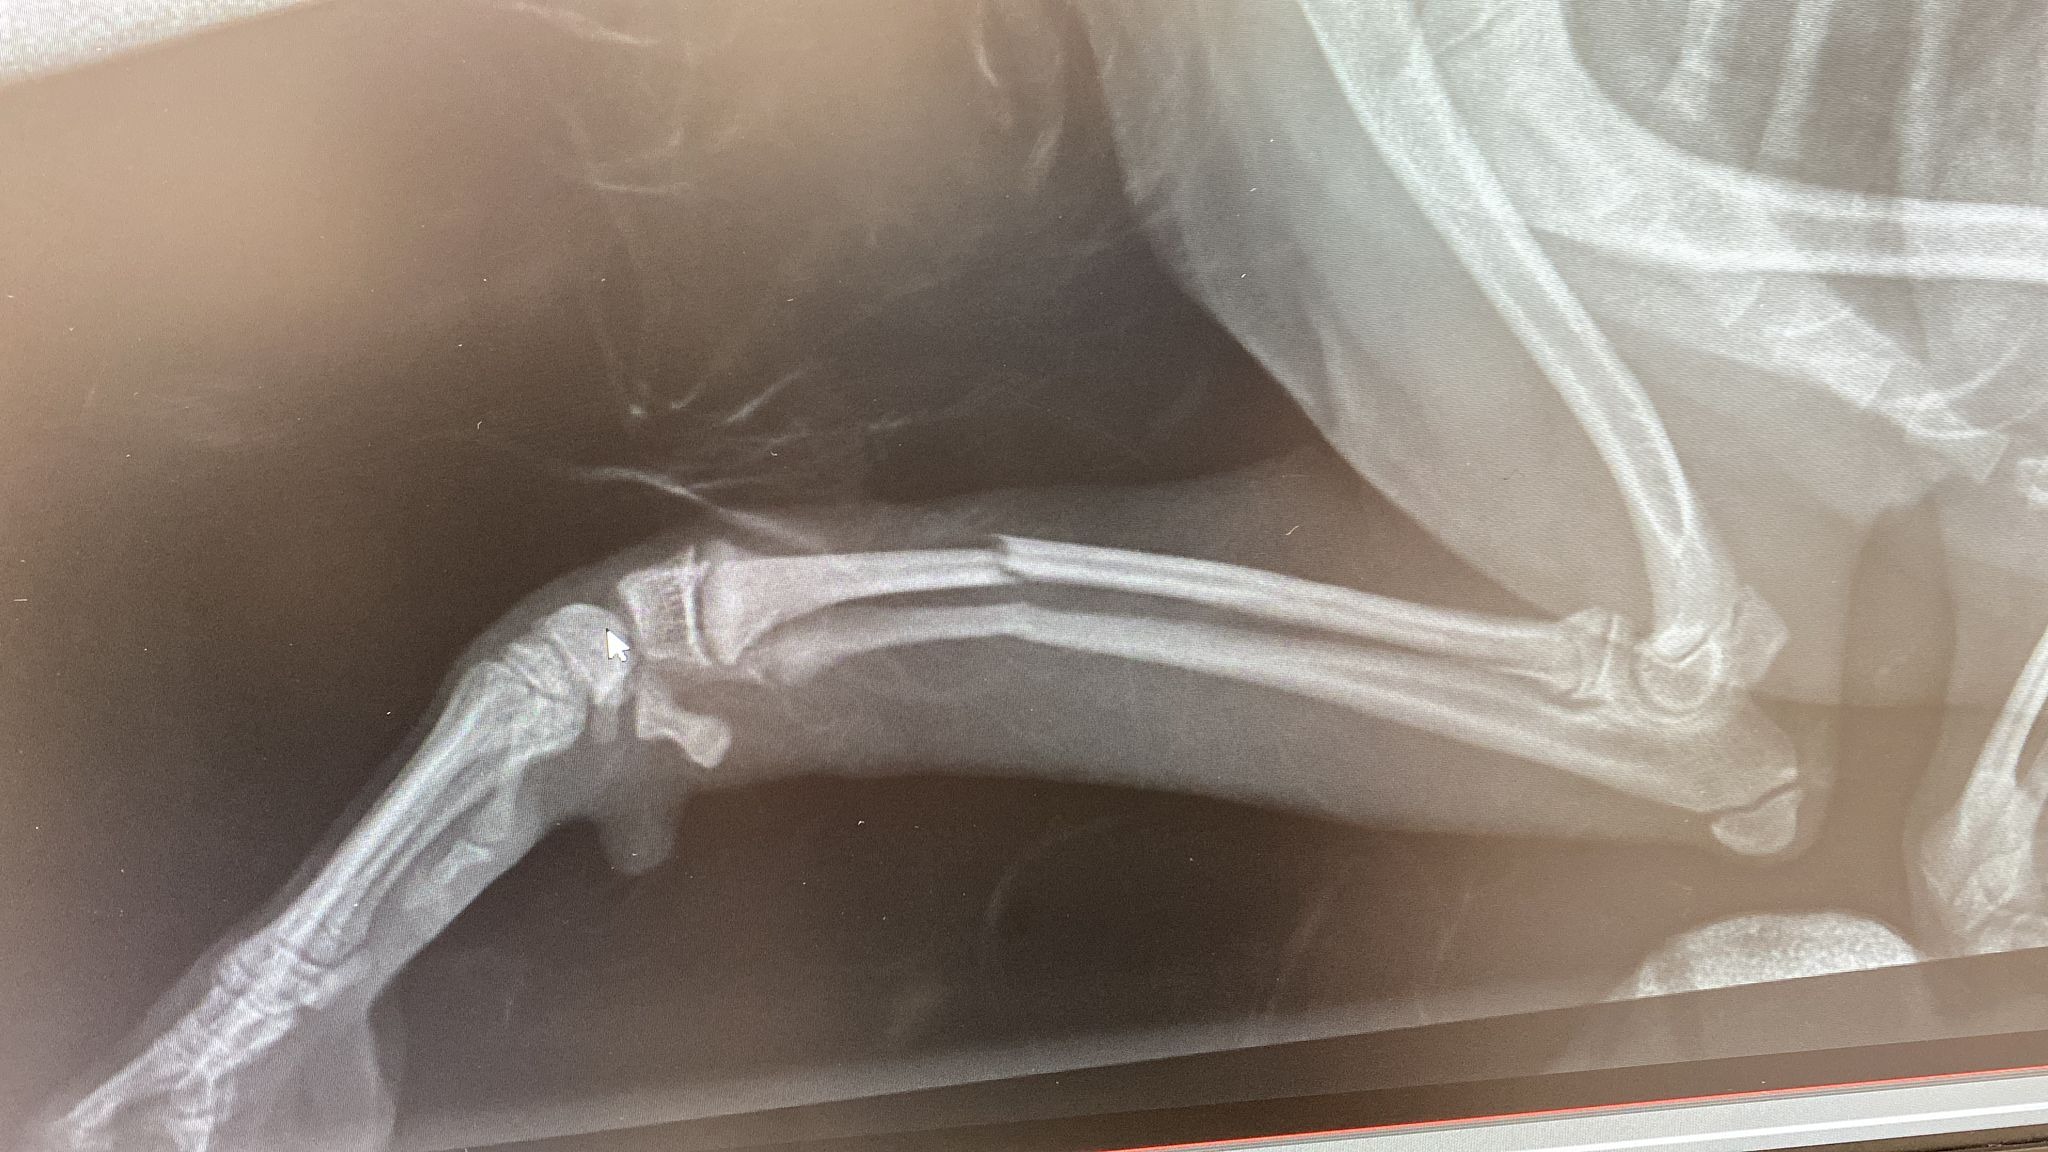

Little snoop dog arrived, he is just a young 12 week old puppy who is loving life in foster with some of his friends. Snoop had an unfortunate accident after jumping from a small box holding his toys. A freak accident or his bones are just not strong enough at the moment - we don't know.

What we do know is, we rushed him straight in to our vets and he had surgery the very same afternoon.

Snoop is now sporting an External Fixator and is having regular checks with the vets to ensure all is going well. We have also added supplements to his diet to strengthen his bones and aid his recovery.